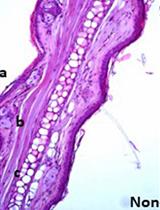

Fungal colonizers of humans have evolved to sense and adapt to niches available in the host (Grahl and Cramer, 2010). Oxygen is a changing environmental parameter. Levels change in different tissues and during different stages of infection and immune activation (Carreau et al., 2011; Wenger et al., 2015). The ability to sustain growth and to survive in low oxygen environments has been linked to virulence in several fungi (Shepardson et al., 2013; Gresnigt et al., 2016; Pradhan et al., 2018). We have developed a protocol to follow the generation of hypoxia in a mouse infected with C. albicans (Lopes et al., 2018). We chose subdermal infection as a local, non-disseminated model of mycosis with acute onset which allows analysis of hypoxia in a confined space, where C. albicans and host cells interact (Urban et al., 2009; Santus et al., 2018). Thereby, natural variation of oxygen levels in other tissues can be eliminated and secondary effects from distant locations arising in systemic infection can be avoided. During infection, hypoxia is created mainly by neutrophil influx to the site of infection. Neutrophil extravasation and the activation of oxygen-consuming enzymes create environments with low oxygen levels. In turn, C. albicans exploits this environmental shift to avoid immune recognition by changing cell wall composition leading to masking of recognized entities (Lopes et al., 2018).